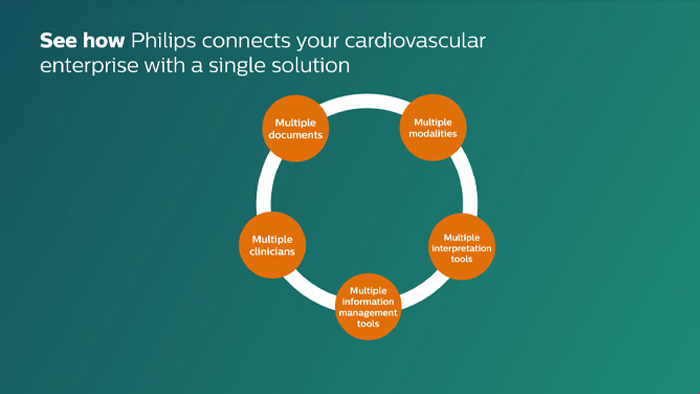

IntelliSpace Cardiovascular

IntelliSpace Cardiovascular is designed to help streamline workflow and improve operational performance throughout the cardiovascular care continuum.